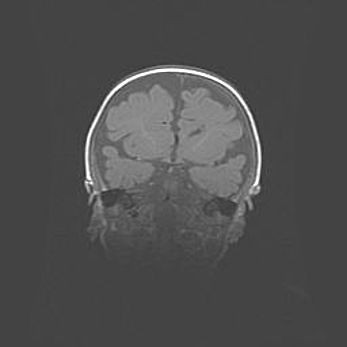

Сообщающаяся гидроцефалия. Кистозная энцефаломаляция головного мозга.

Возраст: 3 месяца 4 дня

Вес: 3100 г

Пол: женский

Окружность головы: 34 см

Срок гестации: 31 неделя

Кистозная энцефаломаляция головного мозга - одна из форм поражения головного мозга в детском возрасте. Характеризуется возникновением множественных и распространённых кист в коре, белом веществе и подкорковых образованиях головного мозга у плодов, новорождённых и детей раннего возраста. Развитие кистозной энцефаломаляции связано с внутриутробной асфиксией и гипотонией, родовой травмой, тромбозом синусов, пороками развития сосудов, инфекциями, сепсисом и другими причинами. Наиболее значимые инфекционные агенты: вирусы простого герпеса, цитомегалии, краснухи, токсоплазмы, энтеробактерии, золотистый стафилококк и другие.